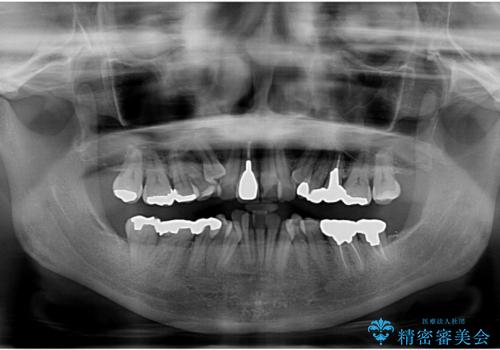

50代女性 八重歯を矯正治療 歯並びの中等度のがたつき

- 八重歯の矯正を希望されて来院。

歯は入りきらないため、通常の抜歯矯正を行いました。

歯がご年齢的に動きにくいため、被せ物のやり替えを含めて治療期間の短縮を図りました。

矯正治療自体は2年半、虫歯治療等で1年ほどかかっています。

詰め物や被せ物のやり替えも併せて行っているため、治療期間を比較的短縮できました。